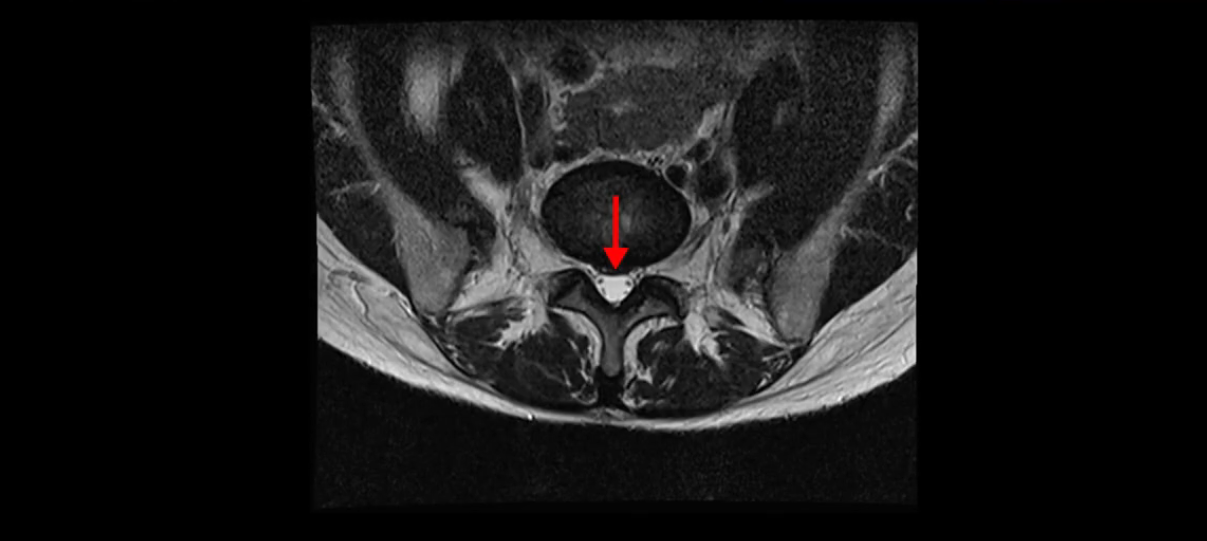

이분 MRI를 보시면 두 마디의 퇴행성디스크가 있습니다. 그리고 디스크가 조금씩 밀려 나와 있고요. 그런데 디스크 탈출 정도는 두 마디 다 심하지 않습니다. 4번 5번에는 디스크 탈출이 약간 있고,

척추관협착도 약간 진행이 되고 있고요.

또한 양쪽 신경 가지가 빠져나가는 추간공은 매우 넓은 상태입니다.

중요한 것은 이 정도 경미한 탈출과 협착으로는 양쪽 다리가 저리고 아플 수가 없습니다.

이분 MRI를 보시면 퇴행성디스크가 있고 약간의 협착이 있지만 이 정도의 퇴행성디스크와 협착으로는 신경이 눌려서 양쪽 다리가 저리고 아픈 증상이 나올 수가 없습니다. 그래서 MRI와 이 환자분의 다리 증상이 매치가 안 된다고 하는 의사들이 많은 겁니다.